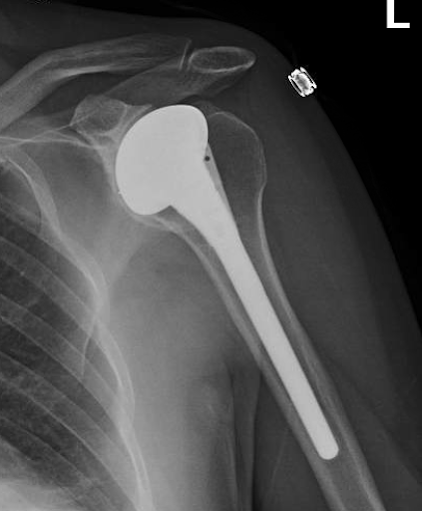

He apparently was not pleased with his functional result so this was revised to an anatomic total shoulder five years later.

Four years after his total shoulder he was having problems and had this x-ray taken

Five years after his total shoulder he presented to our office with a painful stiff shoulder. The x-rays at the time of his visit are shown below showing thinning of the radiographic space of the glenoid component and medial erosion of the glenoid bone.